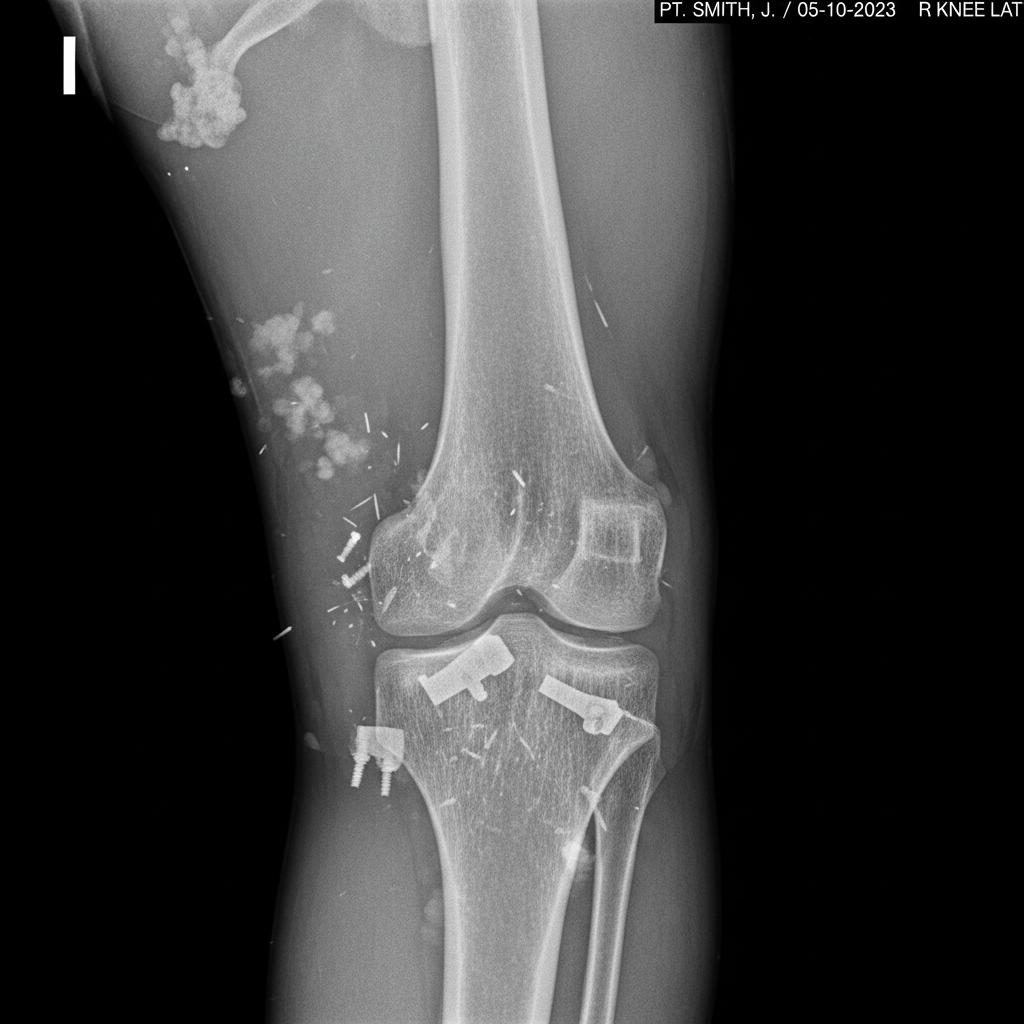

Obecnie diagnostyka zwichnięć opiera się na szybkich, precyzyjnych badaniach obrazowych: USG, RTG, MRI. Coraz częściej do analizy zdjęć wykorzystywane są algorytmy sztucznej inteligencji, które wspierają lekarzy w wychwytywaniu subtelnych zmian.

Nowoczesne metody pozwalają na wykrycie nawet mikrouszkodzeń, które dawniej pozostawały niewidoczne. Dzięki temu leczenie staje się bardziej celowane, a skuteczność rehabilitacji rośnie.